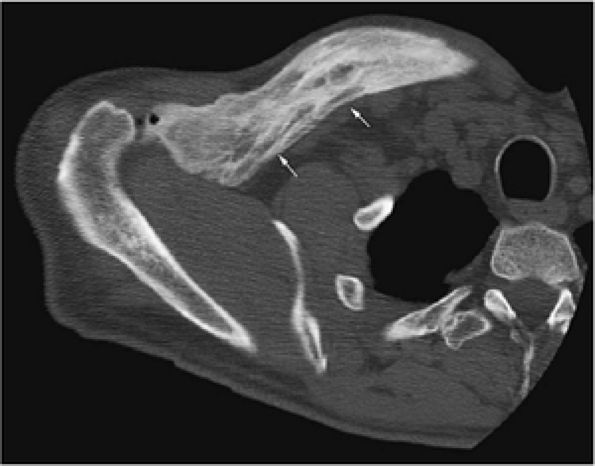

FIGURE 13.31 ● High-grade lymphoma of bone. (A) Marrow involvement of the distal femur is hypointense on a coronal T1-weighted image (arrows). (B) The extent of marrow involvement is better seen on a sagittal STIR image (white arrows). Peritumoral edema and soft-tissue component are hyperintense (black arrowheads). (C) Large associated soft-tissue component is seen on an axial fat-suppressed T2-weighted image (arrows). (D) Axial CT image obtained for biopsy shows destruction of the distal femur with pathological fracture (arrow). (E) Osseous destruction with soft-tissue component is demonstrated (arrows).